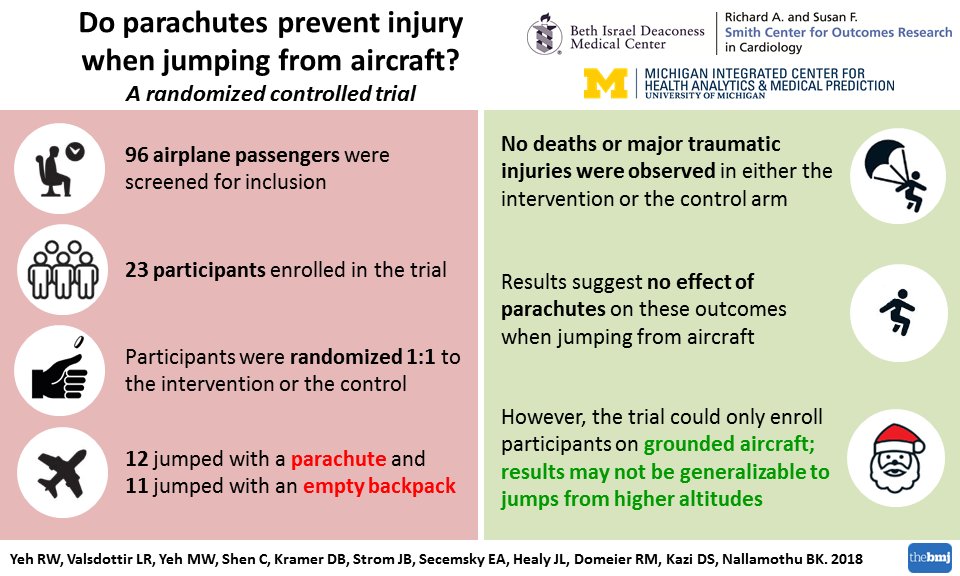

A nice explanation of the impetus behind and lessons of the

#PARACHUTETrial by@SmithBIDMC@kardiologykazihttps://twitter.com/kardiologykazi/status/1074796365685739520 … ಧನ್ಯವಾದಗಳು. Twitter ಇದನ್ನು ನಿಮ್ಮ ಕಾಲರೇಖೆಯನ್ನು ಉತ್ತಮಗೊಳಿಸಲು ಬಳಸುತ್ತದೆ. ರದ್ದುಗೊಳಿಸುರದ್ದುಗೊಳಿಸು

Groundbreaking Study: The

#PARACHUTETrial – The World’s First Multi-Center Block Permutation Randomized Control Trial of Parachute vs No-Parachute While Jumping from an Aircraft. Watch my interview with@rwyeh@kardiologykazi@duanepinto here: https://cardiologynownews.org/groundbreaking-study-the-parachute-trial-the-worlds-first-multi-center-block-permutation-randomized-control-trial-of-parachute-vs-no-parachute-while-jumping-from-an-aircraft/ …pic.twitter.com/bf1IC966dR ಧನ್ಯವಾದಗಳು. Twitter ಇದನ್ನು ನಿಮ್ಮ ಕಾಲರೇಖೆಯನ್ನು ಉತ್ತಮಗೊಳಿಸಲು ಬಳಸುತ್ತದೆ. ರದ್ದುಗೊಳಿಸುರದ್ದುಗೊಳಿಸು

Groundbreaking research out today from

@SmithBIDMC: https://bit.ly/2UFFOFg#PARACHUTETrial#XmasBMJ@bmj_latestpic.twitter.com/G1m9Z8Vttc ಧನ್ಯವಾದಗಳು. Twitter ಇದನ್ನು ನಿಮ್ಮ ಕಾಲರೇಖೆಯನ್ನು ಉತ್ತಮಗೊಳಿಸಲು ಬಳಸುತ್ತದೆ. ರದ್ದುಗೊಳಿಸುರದ್ದುಗೊಳಿಸು

Before the

#PARACHUTETrial@bmj_latest convinces you to skydive with a placebo, you may want to take a look at the fine print. Aren’t all RCTs ultimately a leap of faith? http://bit.ly/2Ev1oqW@bnallamo@rwyeh@SmithBIDMC@CMichaelGibson@DocStrompic.twitter.com/elMEAyNvaJ ಧನ್ಯವಾದಗಳು. Twitter ಇದನ್ನು ನಿಮ್ಮ ಕಾಲರೇಖೆಯನ್ನು ಉತ್ತಮಗೊಳಿಸಲು ಬಳಸುತ್ತದೆ. ರದ್ದುಗೊಳಿಸುರದ್ದುಗೊಳಿಸು

“Opponents of evidence-based medicine/no one would perform a randomized trial of parachute use..shown that it is possible to randomize participants to jumping from an aircraft with versus without parachutes/had to screen many more individuals to identify willing participants.”

https://twitter.com/docstrom/status/1073272264823631873 …

https://twitter.com/docstrom/status/1073272264823631873 … ಧನ್ಯವಾದಗಳು. Twitter ಇದನ್ನು ನಿಮ್ಮ ಕಾಲರೇಖೆಯನ್ನು ಉತ್ತಮಗೊಳಿಸಲು ಬಳಸುತ್ತದೆ. ರದ್ದುಗೊಳಿಸುರದ್ದುಗೊಳಿಸು

This tweet understates the work and effort

@rwyeh@bnallamo and colleagues at@SmithBIDMC &@UM_MiCHAMP put into making this a reality (it was after all running an RCT). Deeply appreciative for their leadership and efforts to make this happen and for@bmj_latest and their humor.https://twitter.com/rwyeh/status/1073269720680488965 … ಧನ್ಯವಾದಗಳು. Twitter ಇದನ್ನು ನಿಮ್ಮ ಕಾಲರೇಖೆಯನ್ನು ಉತ್ತಮಗೊಳಿಸಲು ಬಳಸುತ್ತದೆ. ರದ್ದುಗೊಳಿಸುರದ್ದುಗೊಳಿಸು

Be sure to check out the pictures of enrollees jumping off planes in the article. 15 years later, the

#PARACHUTETrial gets completed. Happy holidays from@bmj_latest and@SmithBIDMC@UMich@harvardmed.https://twitter.com/CMichaelGibson/status/1073269037071826945 …ಧನ್ಯವಾದಗಳು. Twitter ಇದನ್ನು ನಿಮ್ಮ ಕಾಲರೇಖೆಯನ್ನು ಉತ್ತಮಗೊಳಿಸಲು ಬಳಸುತ್ತದೆ. ರದ್ದುಗೊಳಿಸುರದ್ದುಗೊಳಿಸು -

Our newest publication in

@bmj_latest: https://bit.ly/2UFFOFg . Parachute use did not prevent death or major injury in the first RCT of its kind. Happy holidays from@SmithBIDMC@UM_MiCHAMP!@harvardmed@BIDMChealth@michaelyehmd@YuansongZ@ASE360@BIDMCGenCardspic.twitter.com/lzA9OTMH6Z ಈ ಥ್ರೆಡ್ ತೋರಿಸಿಧನ್ಯವಾದಗಳು. Twitter ಇದನ್ನು ನಿಮ್ಮ ಕಾಲರೇಖೆಯನ್ನು ಉತ್ತಮಗೊಳಿಸಲು ಬಳಸುತ್ತದೆ. ರದ್ದುಗೊಳಿಸುರದ್ದುಗೊಳಿಸು